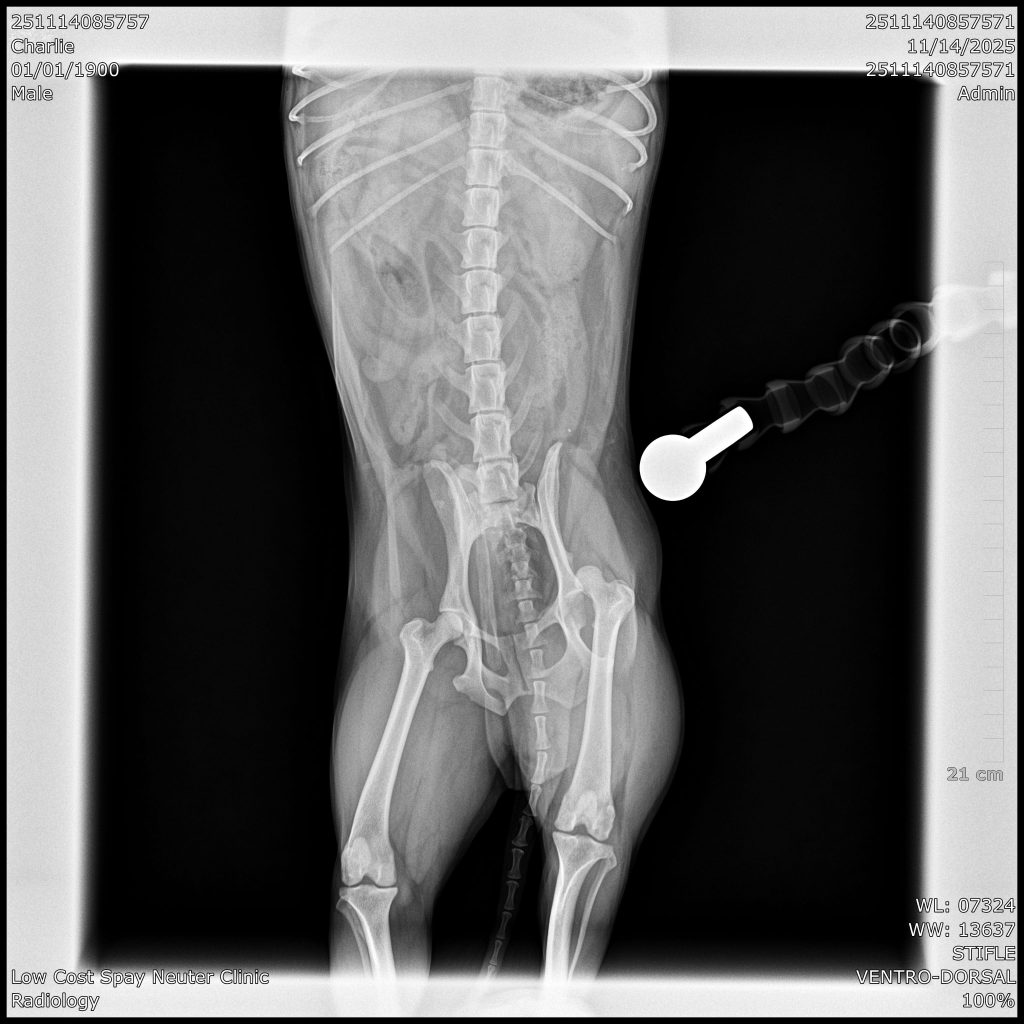

Cranial Cruciate Ligament; (CCL) is one of the most important stabilizers of the knee. It prevents hyperextension, limits internal rotation, and prevents the tibia (shin bone) from sliding forward each time the leg bears weight. When the CCL is damaged, the result is an unstable knee. This instability results in pain and inflammation. Over time, debilitating arthritis develops. Rupture of the cranial cruciate ligament (CCL) of the stifle joint (=knee) is one of the most common orthopedic injury in dogs. It may happen acutely as the result of a true traumatic injury or slow deterioration of the ligament as a dog ages.

TPLO (Tibial Plateau Leveling Osteotomy) surgery stabilizes a dog’s knee joint by altering the angle of the tibial plateau (the top of the shinbone), effectively neutralizing the forces that cause instability when the CCL is damaged. Instead of attempting to repair the torn ligament, TPLO stabilizes the joint by changing the way the femur (thigh bone) and tibia interact during weight-bearing, eliminating the need for a functional CCL.

Price Range $1,200-$3,000